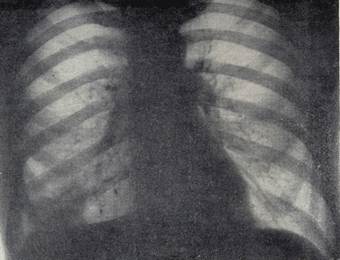

Икота возникает из-за непроизвольных сокращений диафрагмы, которые могут быть вызваны переохлаждением, раздражением или растяжением желудка, стрессом. Продолжительные приступы икоты могут оказаться симптомом серьезных заболеваний: новообразований или воспалительных процессов в брюшной полости, болезней центральной нервной системы и т.д.